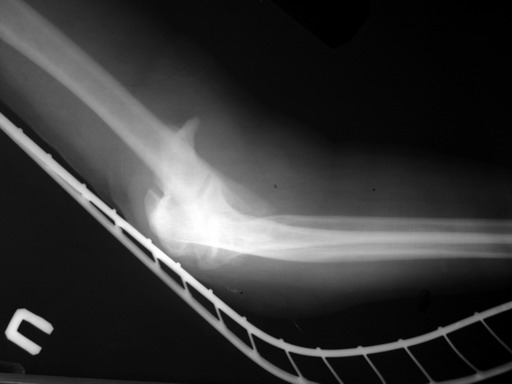

Уважаемые коллеги! Мужчина, 28 лет. 1 сутки назад получил бытовую травму - закрытый чрезмыщелковый перелом правой плечевой кости со смещением. По месту жительства в ЦРБ - репозиция, иммобилизация. Направлен к нам.

Место болезни без особенностей, неврологических и сосудистых расстройств нет. Принято решение об оперативном лечении - чрескостный остеосинтез.Предложения по конструкции АВФ (т.к. мнения расходятся)? Заранее благодарю! С уважением,А.В.ВладзимирскийДонецкий НИИ травматологии и ортопедииДонецк, Украина